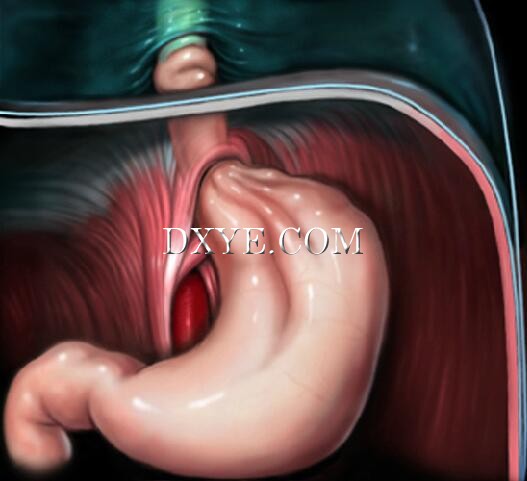

• Stage 2

Stage 2 sliding hiatal hernias occur when the gastroesophageal junction and stomach migrate above the diaphragm.

The EGV can reform above the diaphragm, preventing reflux.

This may explain reports of sliding hiatal hernias without GERD.